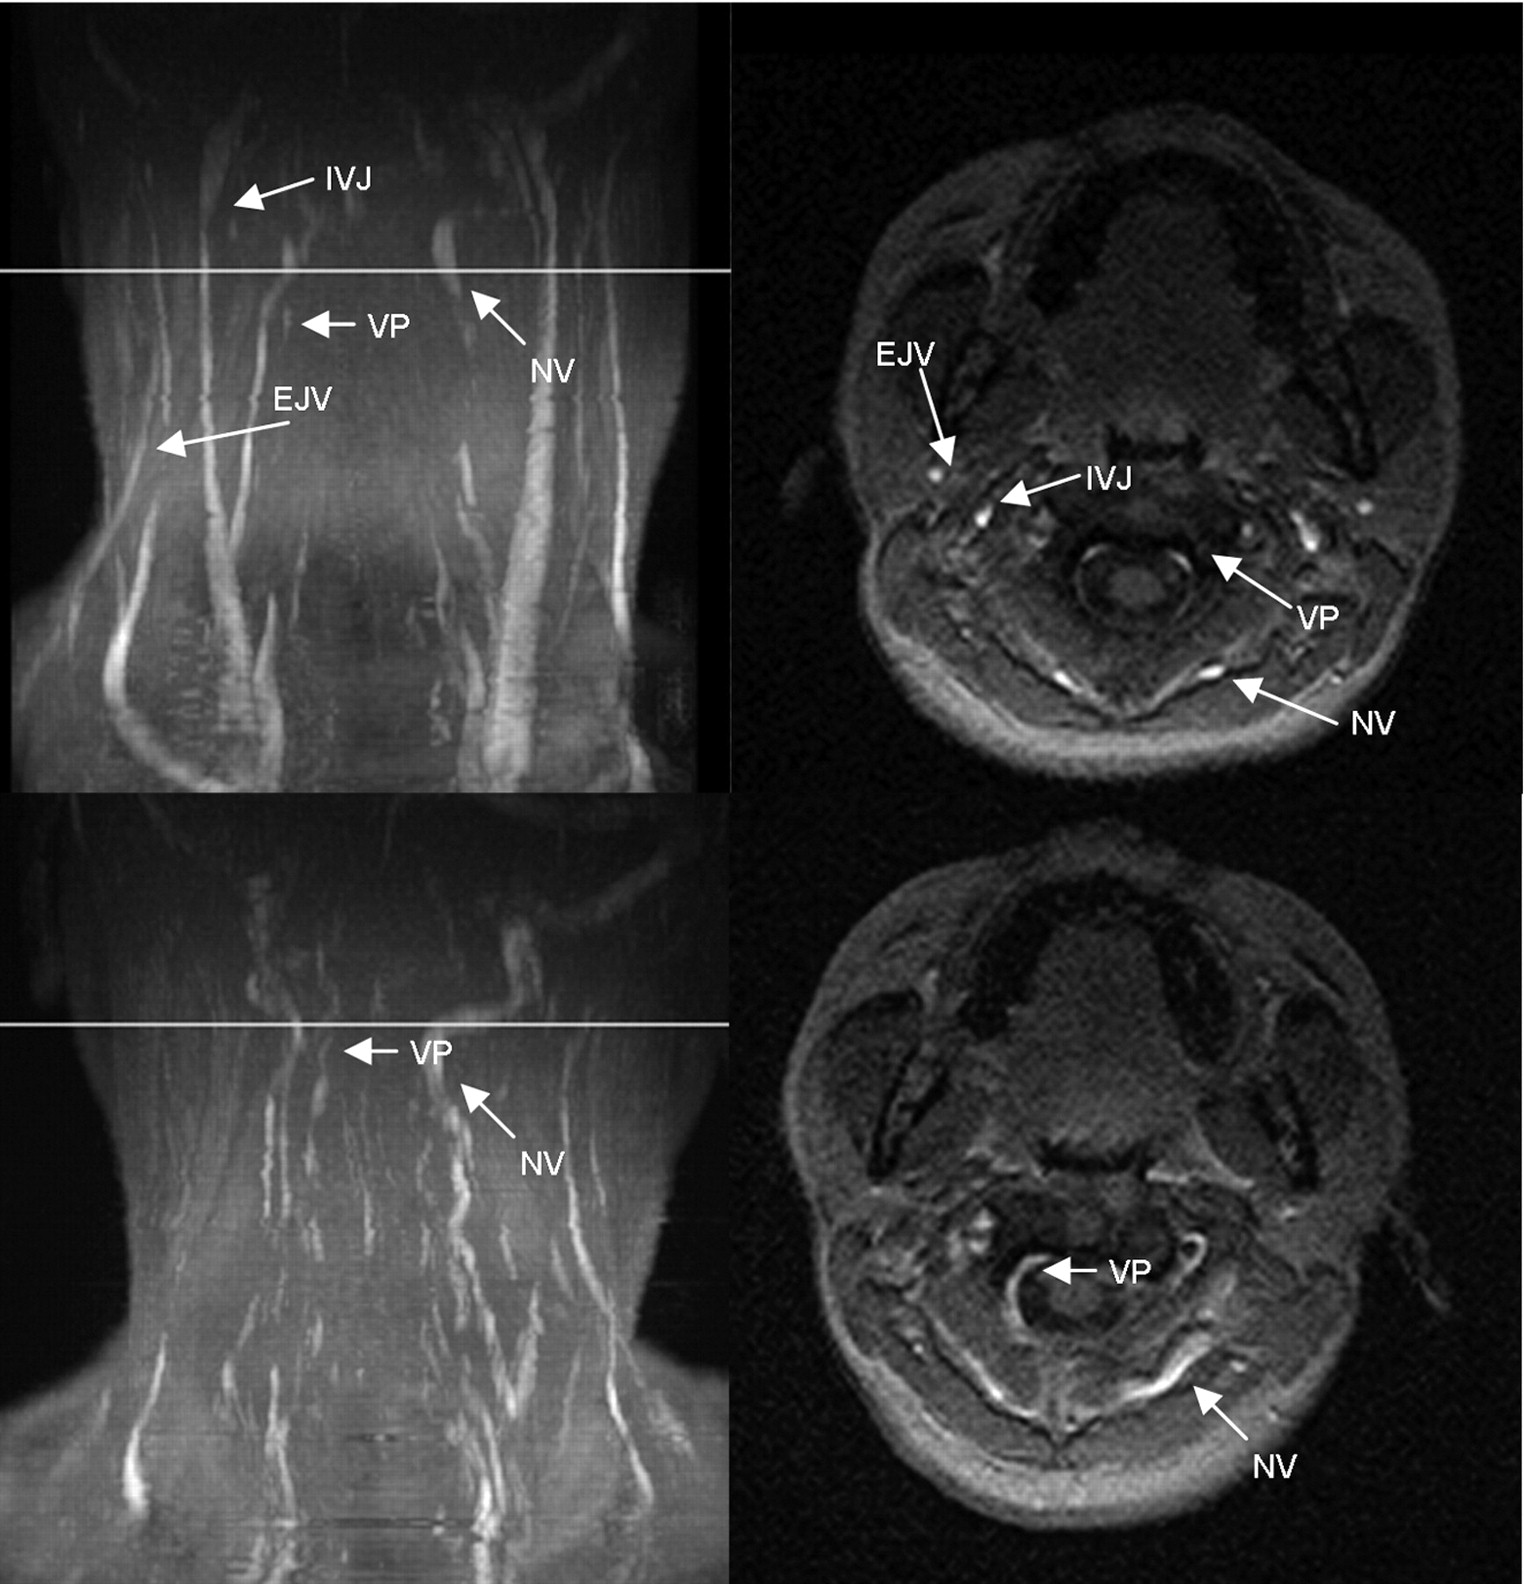

MIP (left column) and axial source images at the level of C4 in the supine (top row) and sitting positions (bottom row) in a healthy volunteer. In the supine position, there is no significant narrowing of the IJV. The EJV, NV, and the VP can be identified in the supine position. In the sitting position, the IJV, EJV, and the NV are much less prominent, whereas the VP is slightly more prominent.

MIP (left column) and axial source images at the level of C2 in supine (top row) and sitting positions (bottom row) in a healthy volunteer. In the supine position, there is a slight narrowing of the IJVs. The EJVs, the NV, and VP can be identified in the supine position. In the sitting position, IJVs and EJVs are no longer visible, whereas the NV are much more prominent. The VP can be identified.

MIP (left column) and axial source images at the level of C2 in supine (top row) and sitting positions (bottom row) in a healthy volunteer. In the supine position, there is a high-grade stricture of the left jugular vein (arrow). The EJV and VP are visible. In the sitting position, only the right IJV is visible (arrowhead). The NV are prominent, and the VP can be identified.

MIP (left column) and axial source images at the level of C2 in supine (top row) and sitting positions (bottom row) in a healthy volunteer. In the supine position, there is a high-grade stricture of the left IJV. The EJV, NV, and VP are visible. In the sitting position, only the right IJV is visible, but narrowed. The VP are prominent, and the NV can be identified.